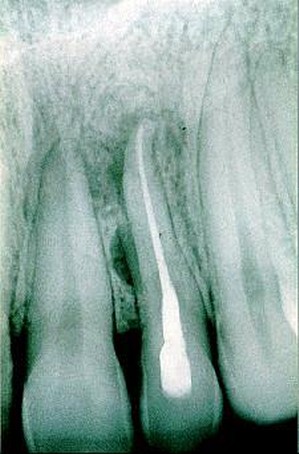

Orthopanthomografické (OPG) a intarorálne RTG snímkovanie je nevyhnutné pre stanovenie presnej diagnózy a plánu ošetrenia, pri preventívnych prehliadkach, ale aj pri bežnom ošetrení. Zobrazí už počiatočné kazy na miestach, ktoré nie sú na prvý pohľad viditeľné. Rovnako je dôležité aj pri endodoncii, teda pri ošetrení koreňových kanálikov, pri zápaloch nervu, pri paradentóze a kývavosti zubov, prípadne posúdení nutnosti extrakcie zuba.

V našej praxi sa pri diagnostike ochorení v dentoalveolárnej oblasti používa zobrazovacia technika, ktorá je neoddeliteľnou súčasťou vyšetrenia pacienta, ako aj následných ošetrení. Zhotovujeme digitálne intraorálne snímky. Ich výhodou je okamžité zobrazenie na monitore počítača, niekoľkonásobne znížená doba expozície, možnosť uloženia záznamu pre porovnanie do budúcnosti, možnosť aktívnej práce so snímkami, zobrazenie detailov, zmena kontrastu, farebné zobrazenie. Tieto snímky majú výrazný informatívny význam pri diagnostike tvrdých tkanív (zuby, kosti), závesný aparát zubov, pre plánovanie protetických prác, celkových sanácií, ale predovšetkým pri plánovaní implantačnej terapie.